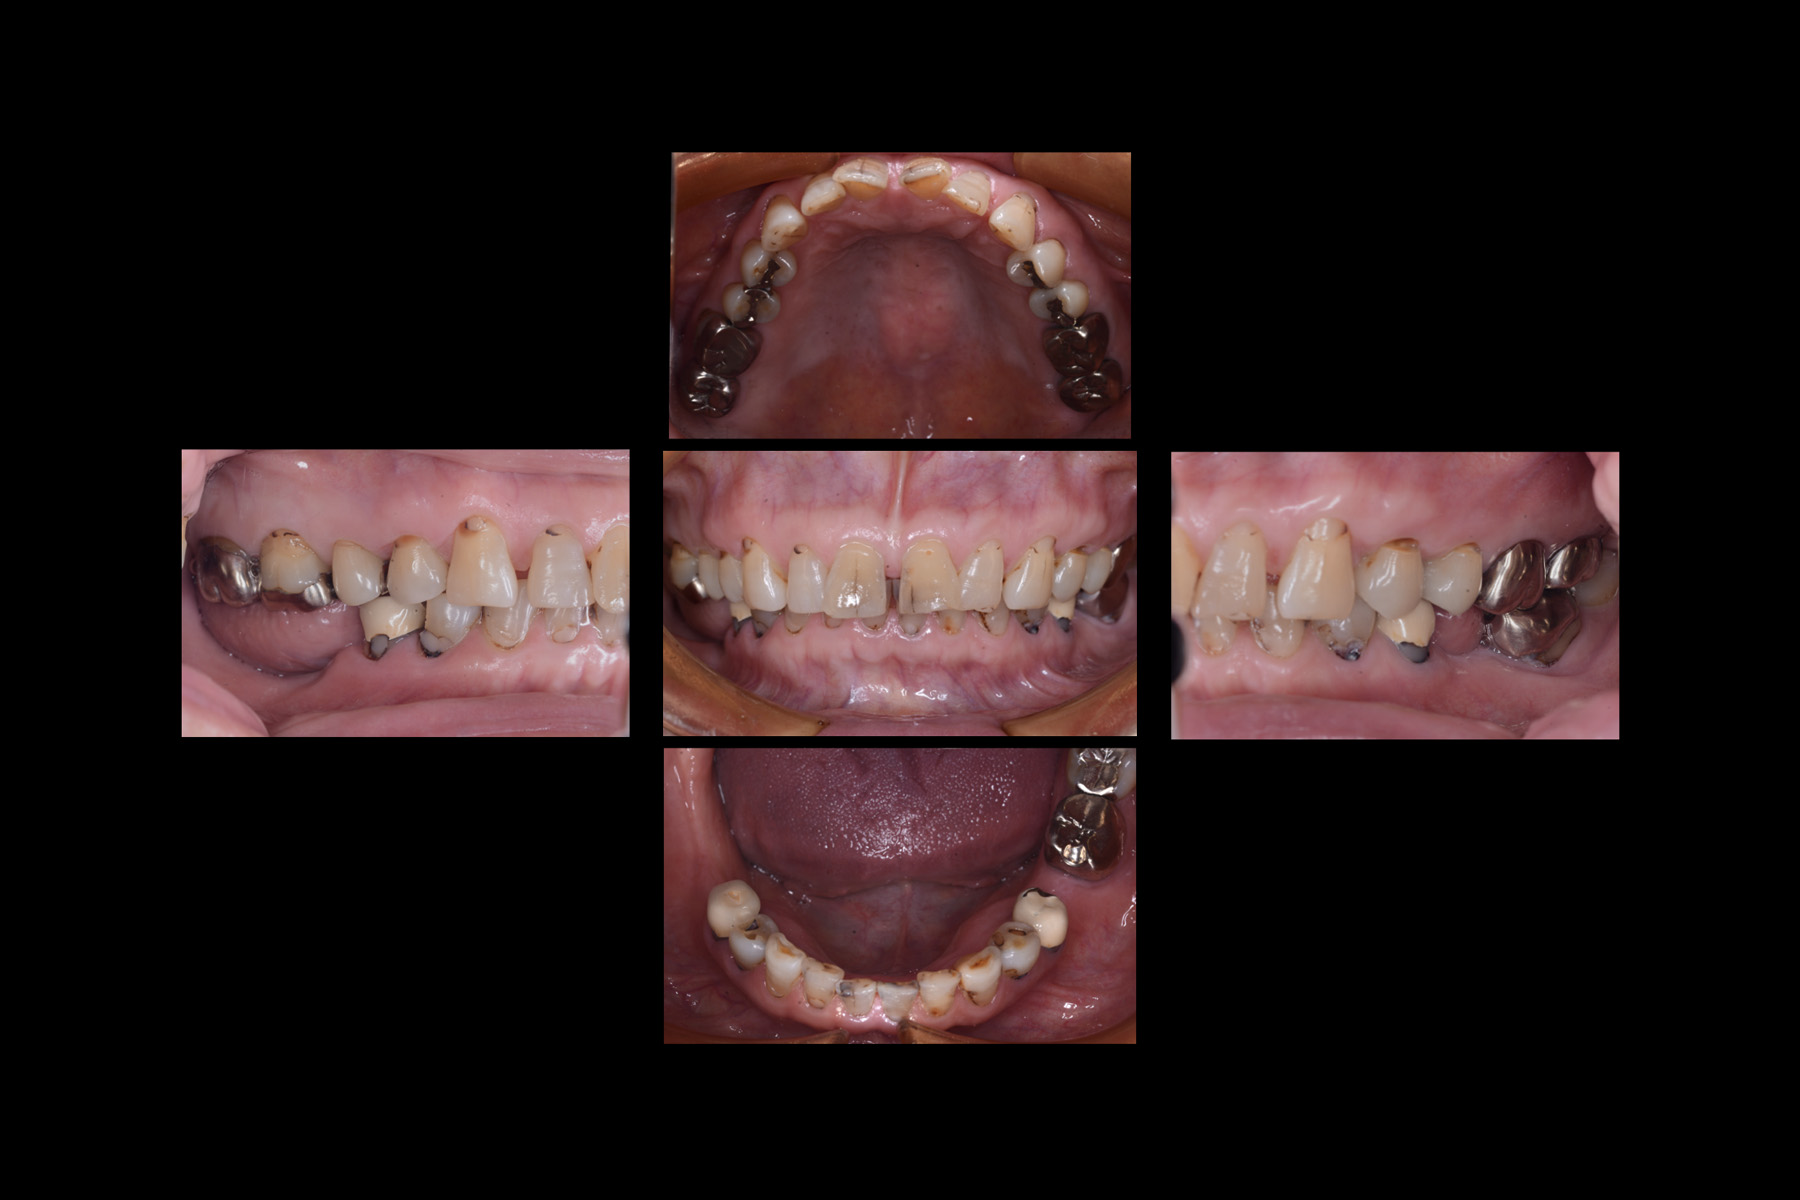

- 主訴

- 審美不良、咀嚼障害

- 期間

- 約1年

- 費用

- 約1,000,000円(税抜)

- 治療内容

- ・全顎補綴

・入れ歯治療

- 治療に伴うリスク

- 噛み合わせを獲得による顎関節症状のリスク